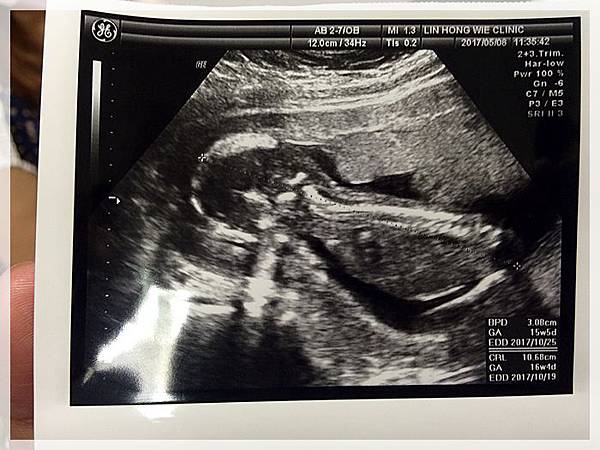

2017.05.08 紜紜6y06m02d 妞妞4y03m29d

今天我們去產檢,來去看樂樂囉![]()

樂樂有乖乖的長大...

醫生叔叔也說確定樂樂是男生不是在下面比讚喔![]()